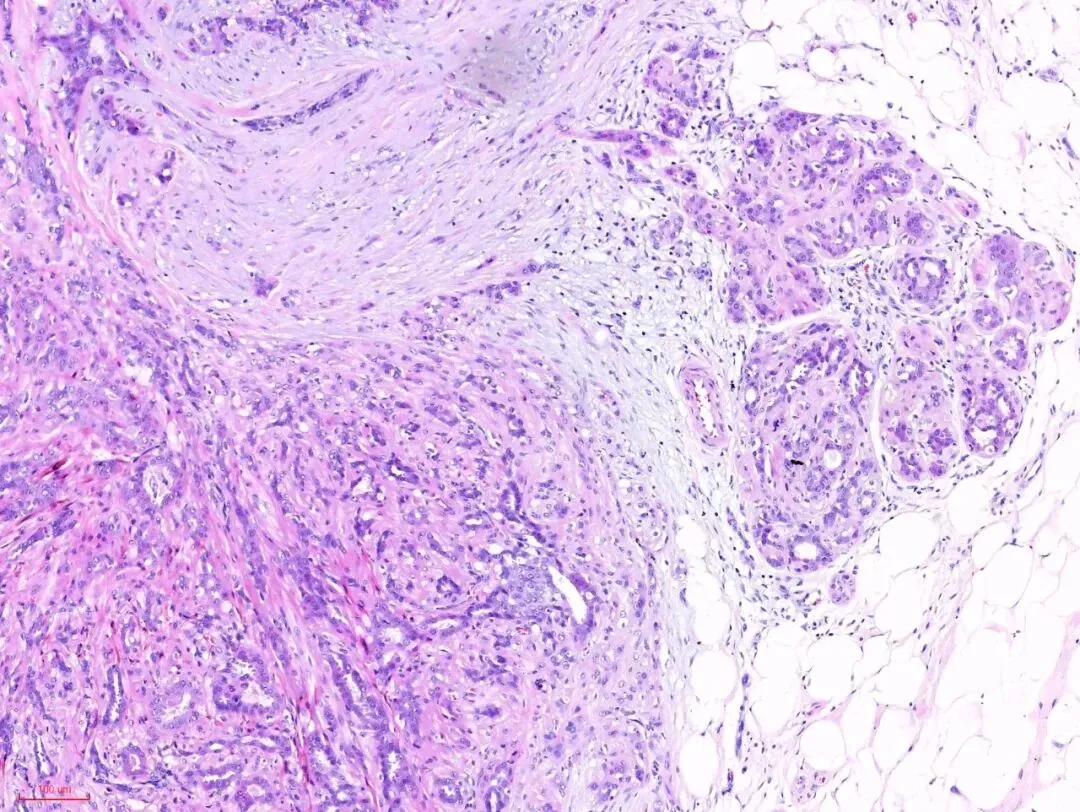

那么下图的结构又怎么理解呢?是浸润性癌吗?

左下角的这些腺上皮与右上角正常的腺上皮细胞是一样的,而左下角腺上皮周围的粉染的条索样的成分与右上角正常小叶的肌上皮成分是一样的,也就是说这部分应该是增生的腺上皮和肌上皮。免疫组化也证实了这一点。

所以,即便是这样的杂乱无章,貌似癌的浸润,也还是良性的,这时应仔细观察细胞的异型性。如果是癌,细胞异型性是很大的,如下图:癌性的间质促纤维反应,也是粉染的,但不像硬化性腺病那样去挤压腺体,而是腺体与间质之间有一些裂隙,更大的区别在于细胞异型性,常有丰富的嗜酸性胞质,有不同的核级,核从规则到多形性,核大深染,核仁明显,核分裂象易见。如下图: